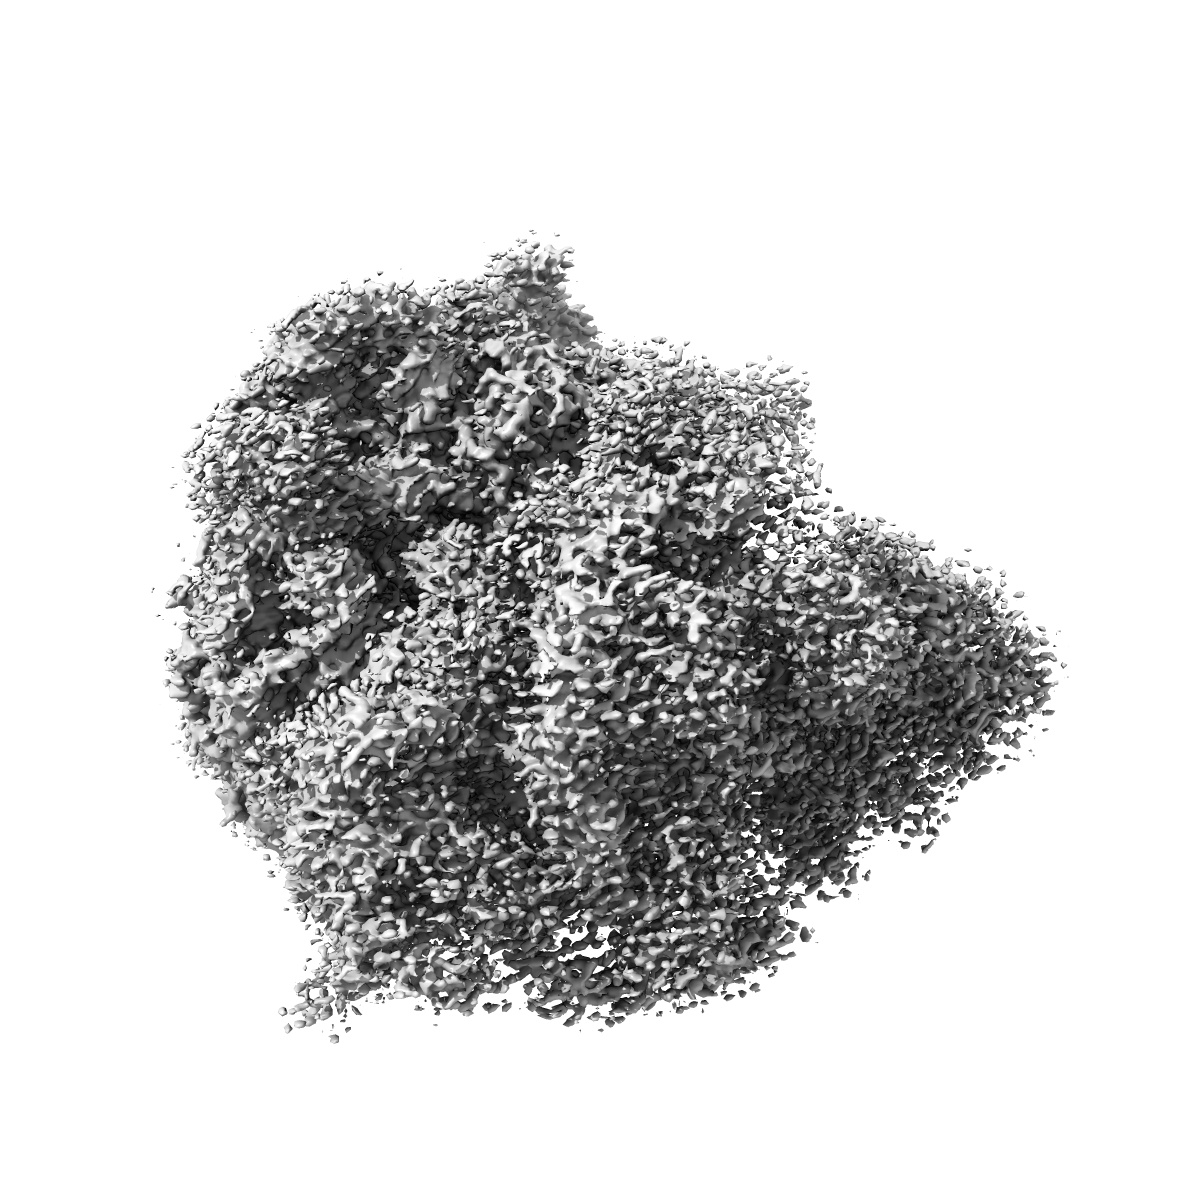

Erythromycin Resistant Staphylococcus aureus 70S ribosome (delta R88 A89 uL22).

EMD-10079

Single-particle

3.58 Å

Sample Organism: Staphylococcus aureus

Sample: Erythromycin Resistant Staphylococcus aureus 70S ribosome (delta R88 A89 uL22) in complex with erythromycin.

Fitted models: 6s13

Deposition Authors: Halfon Y, Matozv D

Exit tunnel modulation as resistance mechanism of S. aureus erythromycin resistant mutant.

Halfon Y, Matzov D, Eyal Z , Bashan A , Zimmerman E, Kjeldgaard J , Ingmer H , Yonath A

(2019) Sci Rep , 9 , 11460 - 11460

PUBMED: 31391518

DOI: doi:10.1038/s41598-019-48019-1

ISSN: 2045-2322